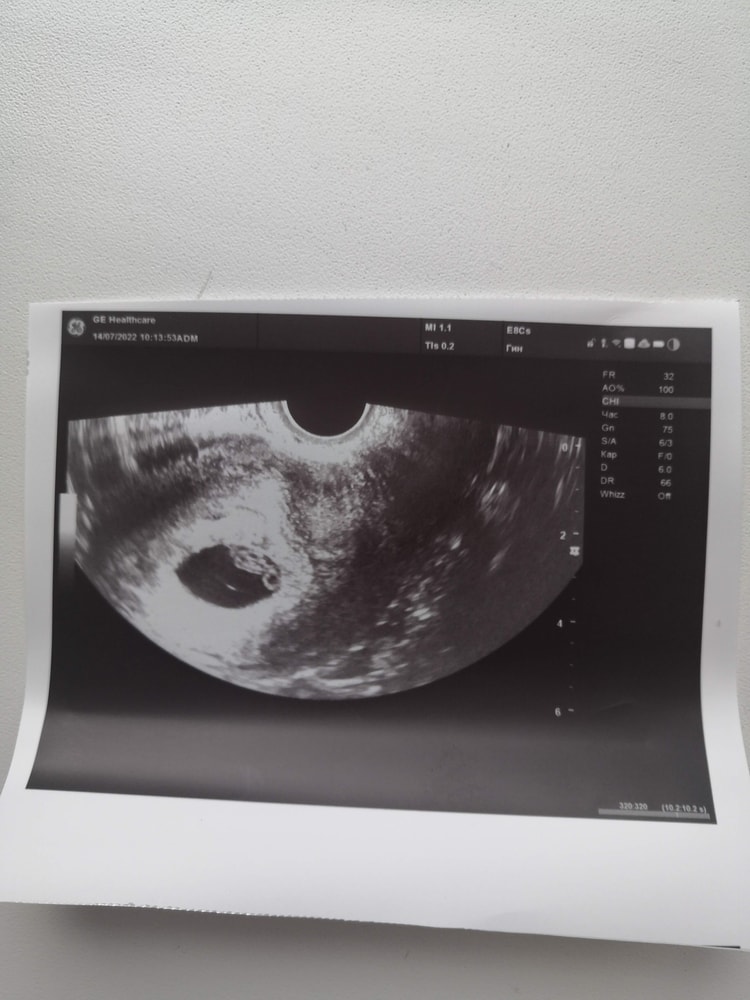

Честно говоря, очень мало похоже на Б (по крайней мере на фото из моего УЗИ так Б не выглядела).

Это УЗИ на 15 день задержки

Не знаю, бывает, что врачи путают кисту с Б, но больше вероятности, что просто киста вырастает вместе с Б на фоне гормонального сбоя. На Вашем фото я бы сказала, что это киста, да и врач бы про Б сказала бы, если б увидела. А вот на фоне чего она выросла... Либо просто, либо Б появится потом.